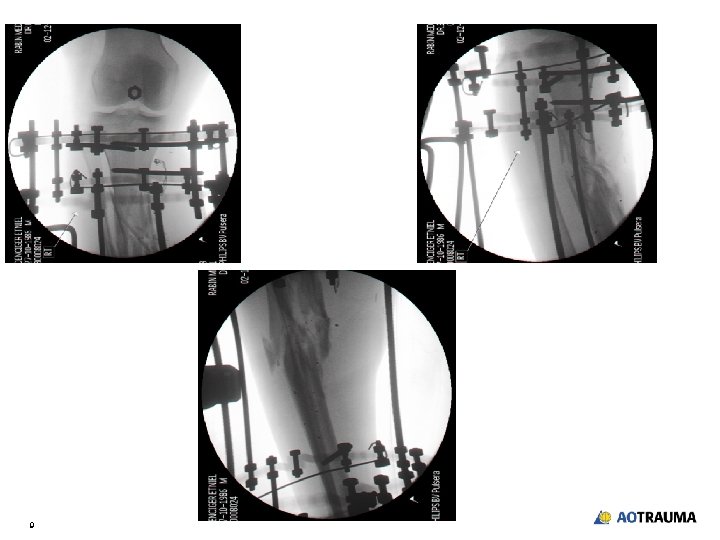

Day of admission • • • 5 Vascular exploration and temporary vascular bypass Debridement and temporary stabilization with external fixator Vein graft reconstruction—popliteal to tibial artery bypass Temporary soft-tissue coverage Broad spectrum antibiotic coverage

After external fixation and vascular repair 6

Day 4 • Local gastrocnemius flap • Definitive fixation - Ring fixator—“Hexapod” 8

9